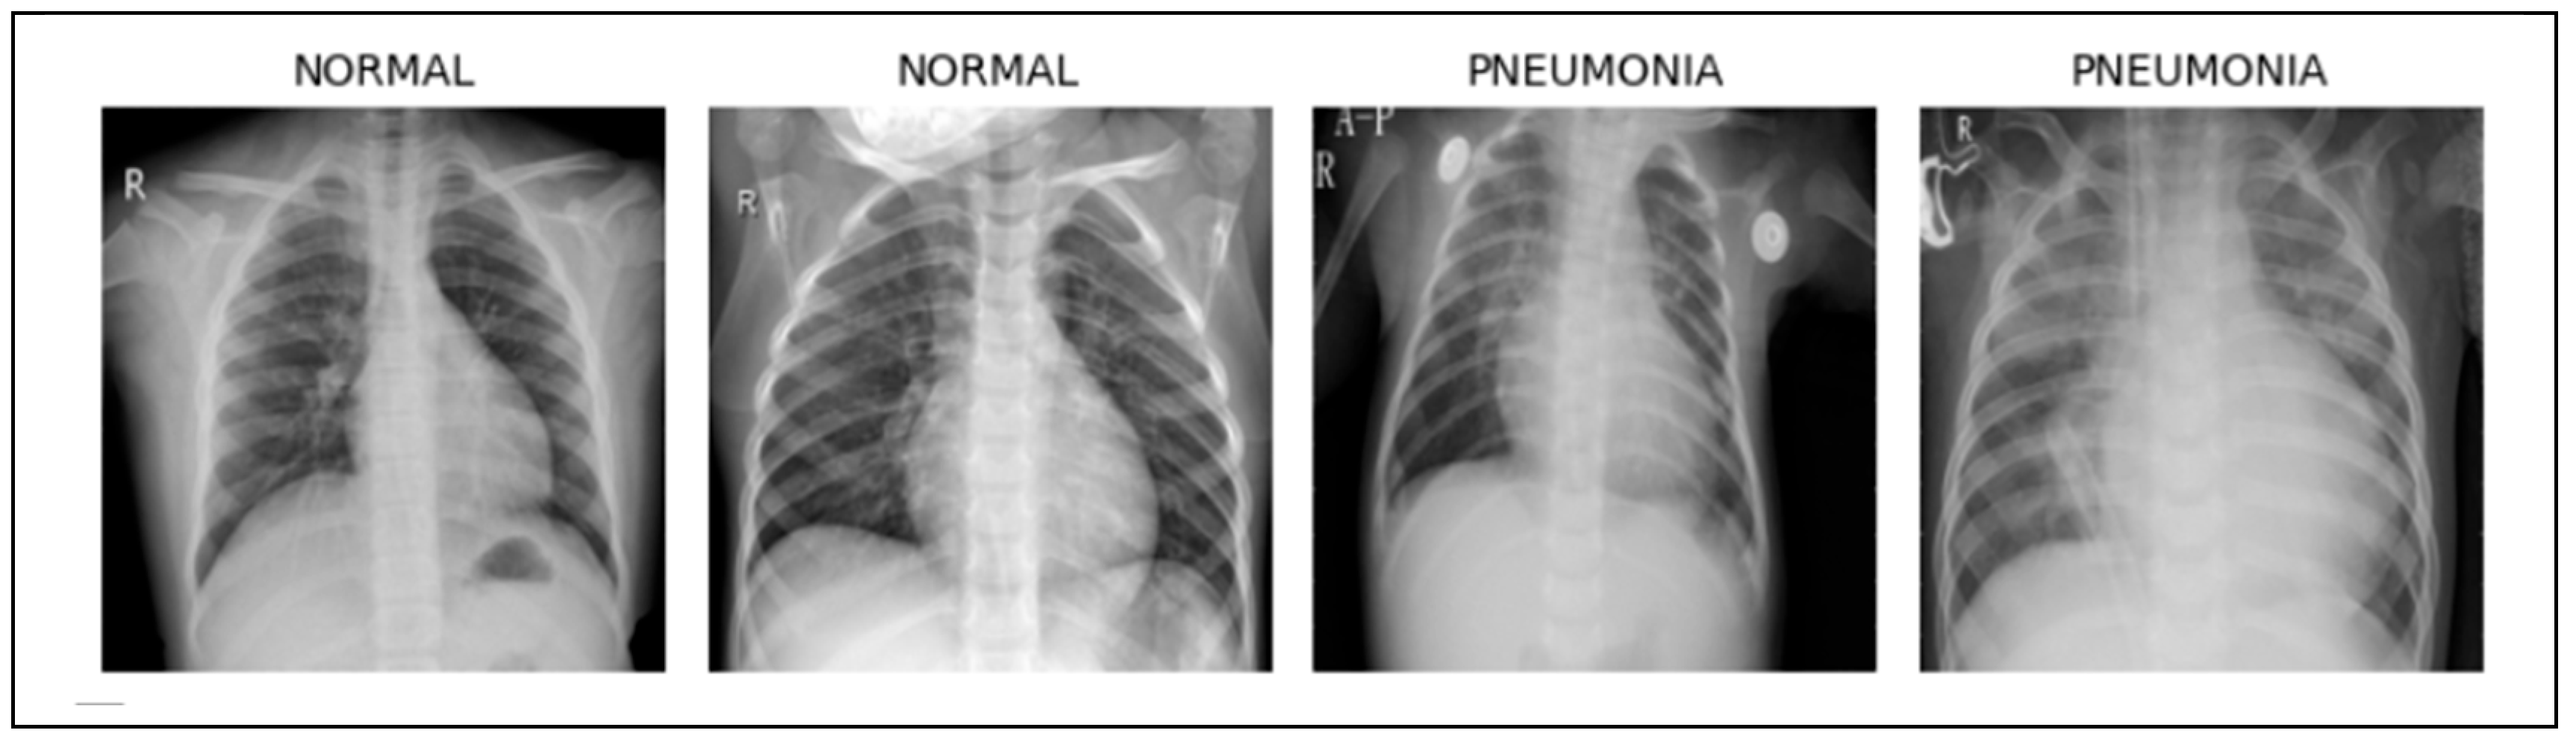

Sample pictures taken from the “Chest X-Ray Images (Pneumonia)” set can be seen in Figure 2. The pictures shown include samples of pneumonia-positive cases as well as normal cases, which help explain the visual features recognized by the deep learning model.

Figure 2. Dataset Visualization and Sample Images.